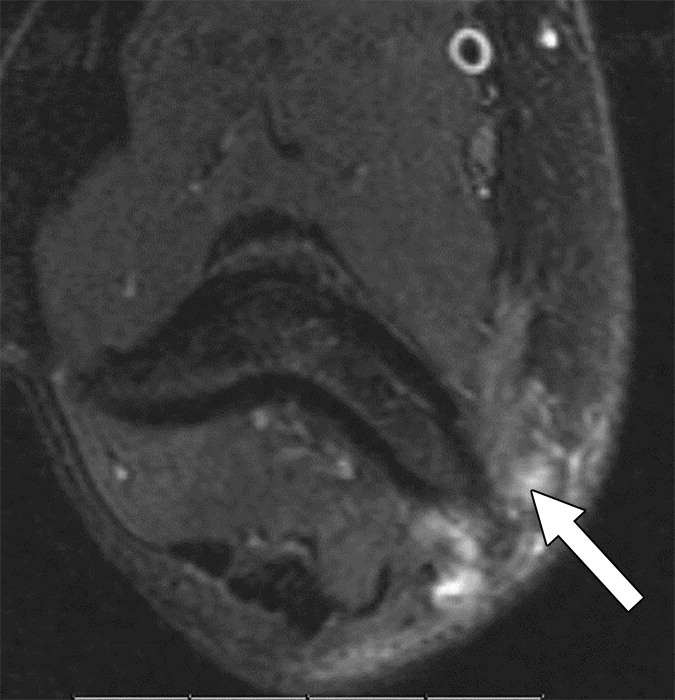

Our retrospective study included 100 patients with nerve imaging examinations and a variety of known clinical diagnoses. Utilizing mutually agreed-upon qualitative benchmarks for classifying and grading peripheral neuropathies, different classes were established to account for the spectrum of underlying pathologies (unremarkable, injury, neoplasia, entrapment, diffuse neuropathy, not otherwise specified, and postintervention state) with subclasses to describe lesion severity or extent. Validation was performed by 11 fellowship-trained musculoskeletal radiologists across 10 institutions, and after initial multimedia training, all 100 cases were blind-presented to readers (Fig. 1).

Offering a uniform lexicon and practical guideline for reporting neuropathic conditions on MRI, ultimately, NS-RADS accuracy for determining milder versus more severe categories per radiologist ranged from 88% to 97% for nerve lesions and from 86% to 94% for muscle abnormalities (Fig. 2).